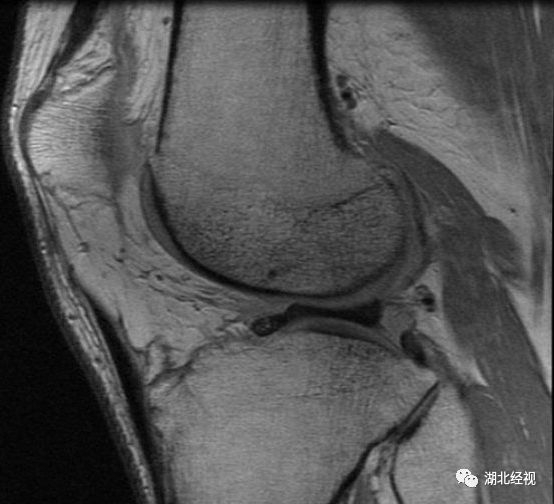

妙龄女为减肥每天锻炼3小时 竟患上“老年病”23岁的王小姐59公斤体重,160的身高。为了让自己身材看起来更苗条,她每天跑步三小时,不料膝关节闹起“罢工”:近两月来跑步时左膝关节总是莫名的疼痛,感觉有力使不出来,有时还有异常弹响。到医院一检查,确诊为左膝外侧盘状半月板并III度损伤。

像王小姐这样的可不在少数,医生表示,这两年随着“汉马”和夜跑族的兴起,盘状半月板患者越来越多。